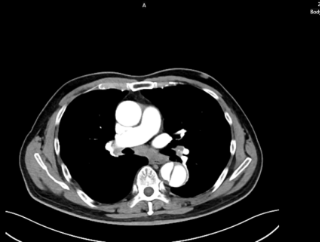

71岁男性,突发剧烈胸痛,既往有长期高血压、糖尿病病史。

五、主动脉夹层诊断

时间就是生命。医生会结合症状,快速进行以下检查:医院会根据CT血管成像(CTA)进行诊断。如确诊为主动脉夹层,则会进行紧急处理,立即镇痛、控制血压和心率(如静脉注射β受体阻滞剂)。